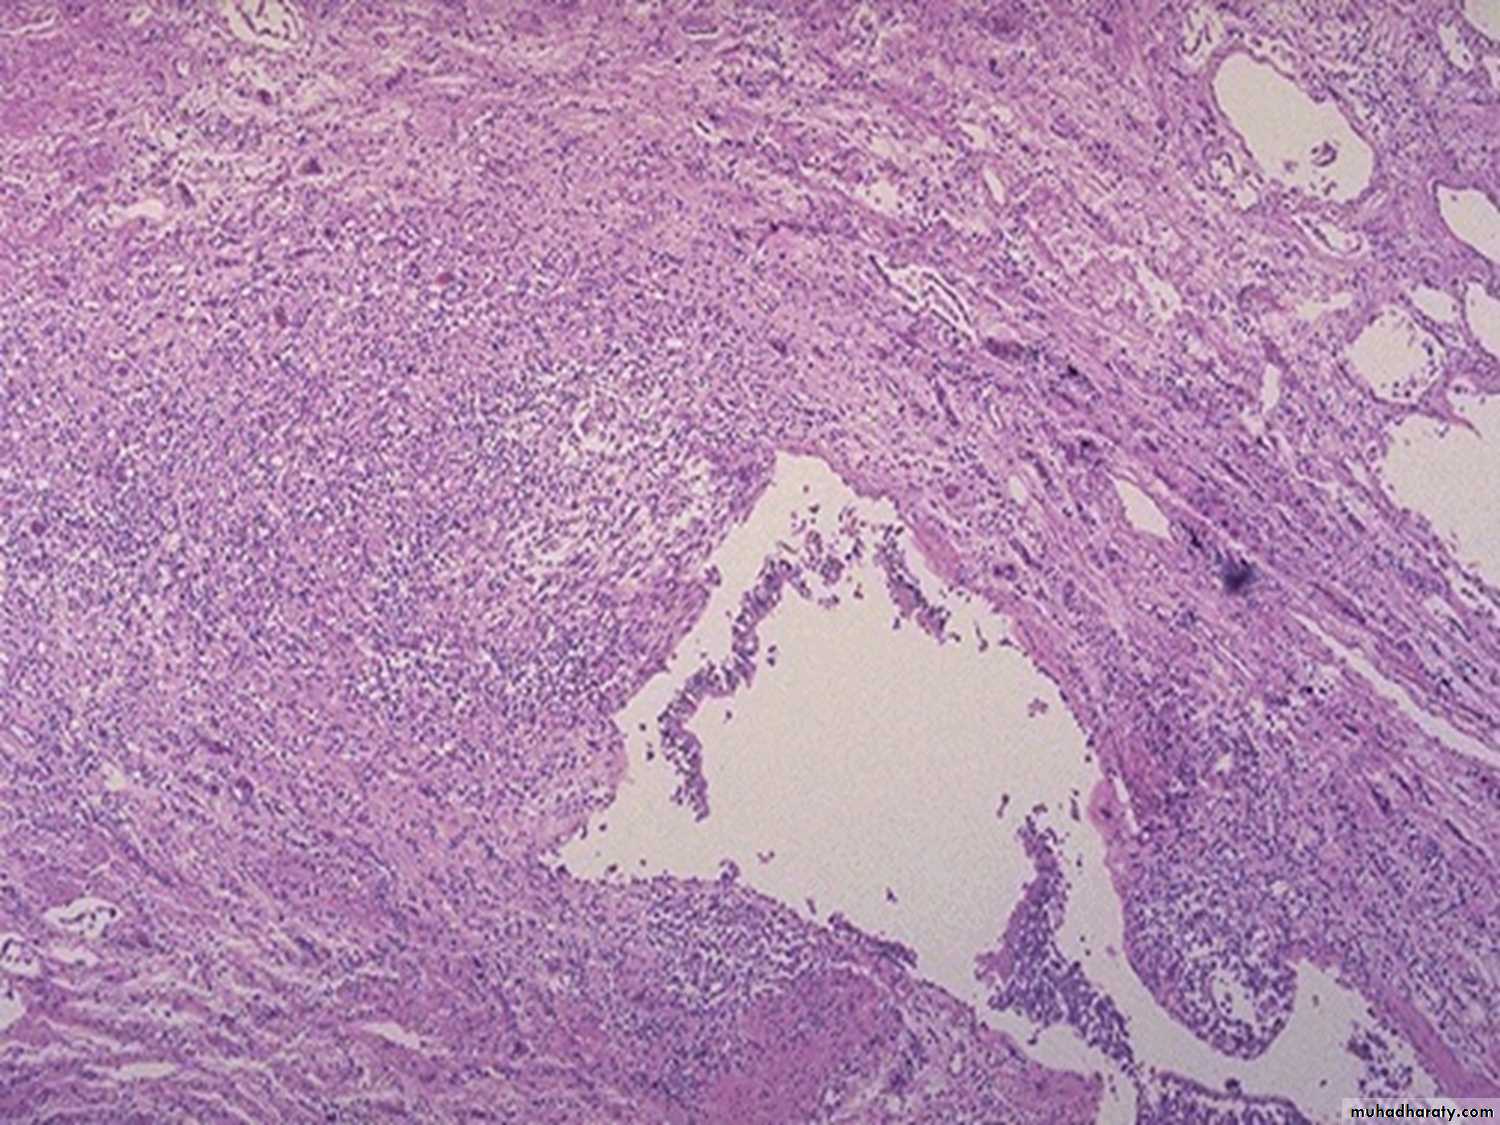

Morphology:

The histological hallmark of sarcoidosis is the presence of non-caseating epithelioid granuloma, irrespective of the organ involved.

These are nodular collection of epithelioid histiocytes, rimmed by an outer zone of lymphocytes (CD4 helper). Scattered multinucleated giant cell may be seen. More peripherally, a layer of fibroblasts is present, which proliferate and lay down collagen that replace the granuloma.Organs involved:

Lungs: In 90% of cases. Multiple granulomas in the interstitium ending in interstitial fibrosis and development of core plumonale.Lymph nodes: 75-90% of cases. Intrathoracic and paratracheal lymph nodes. In 30% of cases peripheral lymph nodes.